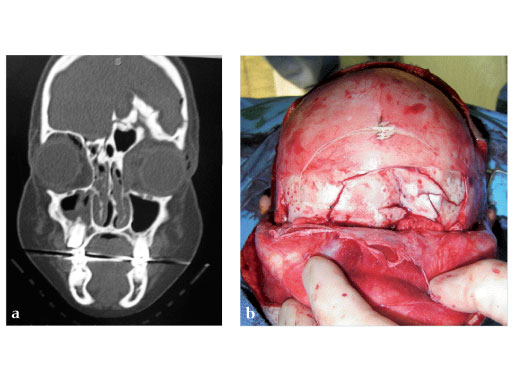

Fig 2ad Highly comminuted panfacial fracture.

Fig 2ad Highly comminuted panfacial fracture (continued).

Case images courtesy of Scott P Bartlett, Philadelphia, US